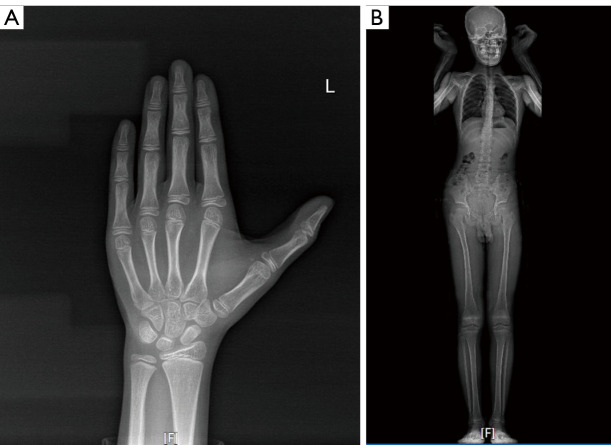

Case description: The patient had facial abnormalities (micrognathia, high-arched palate, microtia, and preauricular tags), a small head-to-body ratio, sensorineural hearing loss, delayed speech development, and cognitive impairment. Exome sequencing identified a splice variant, NM_004247.4:c.492+1del, in the EFTUD2 gene, which was classified as pathogenic according to the guidelines of the American College of Medical Genetics and Genomics (ACMG). AlphaFold 2 predictions indicated that this variant had a significant impact on the protein structure. RNA-sequencing (RNA-seq) further demonstrated that the NM_004247.4:c.492+1del variant led to a pronounced splicing abnormality, causing exon 6 skipping during the transcription process of the EFTUD2 gene.